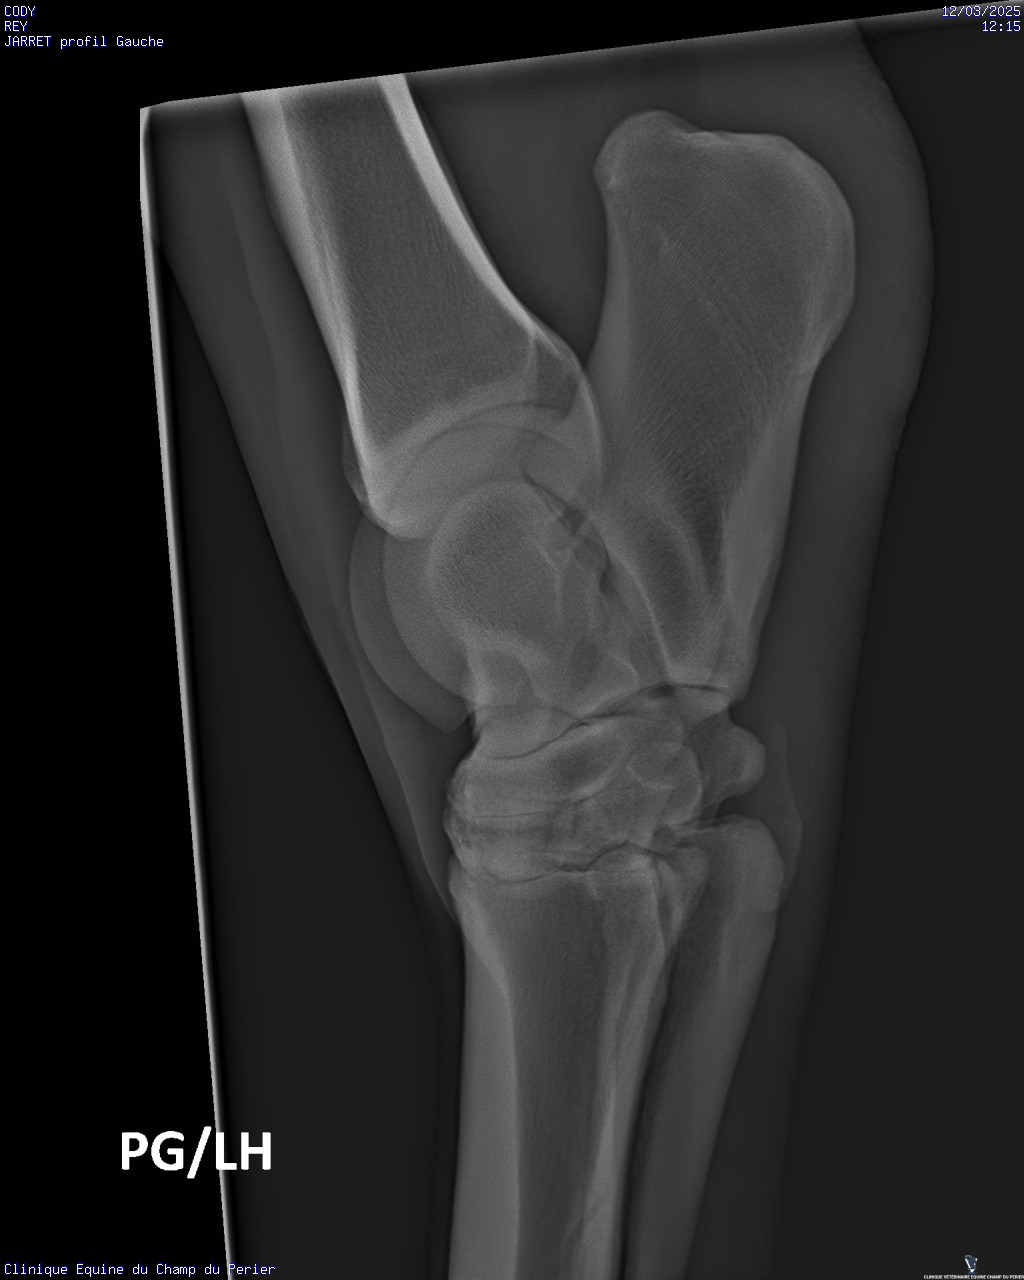

| Dire merci | Voici les résultats : - pieds antérieurs : novembre 2024 : perte de parallélisme entre les 3° phalanges des deux antérieurs et les sabots-parois dorsales ; pieds trop longs en pinces - pieds postérieurs ce jour : très léger défaut de parallélisme entre P3 et parois dorsales des sabots, mais pinces trop longues. Un défaut en phase de correction sou le sabot PG, en ponte de fourchette. On note aussi un ostéophyte au sommet dorsal de P2 sur le PD. - jarrets : on note sclérose des os centraux et troisièmes os des tarses + lyse forte de ces deux os sur le jarret gauche Ccl : comme indiqué sur mon ordonnance il faut : - parer les sabots afin d’obtenir au fur et à mesure le parallélisme entre les 3° phalange et les parois dorsales des sabots ; parer les pinces des sabots au plus court - poser des fers qui seront bien reculés et donneront de la surface d’appui en talons, sur les deux antérieurs - soulager la douleur pour les deux mois à venir avec Equioxx° un comprimé par jour. Le contrôle des enzymes rénales – normales – fait se jour le permet. - traiter CODY avec des biphosphonates (Osphos°, voire Tildren°) |

| Dire merci | C'est quoi une forte lyse ? C'est ça qui lui avait fait gonflé le jarret ? Finalement pas de fourbure ? (Tant mieux) (Et pour les anomalies que tu avais entouré en bleu sur les anciennes radio ? Il a dit quelque chose de spécial ?) |

| Dire merci | C'est pas une perte d os un peu comme l'osteoporose? Et donc un.machin lié à arthrose? Un veto pour expliquer? Message édité le 12/03/25 à 21:18 |

| Dire merci | Oui l’ostéolyse c’est la destruction du tissu osseux. Mais il n’avait jamais eu de radios du jarret G dans les multiples examens déjà faits? Parce que c’est vraiment pas beau là ![]() |

| Dire merci | Mais il n’avait jamais eu de radios du jarret G dans les multiples examens déjà faits? Parce que c’est vraiment pas beau là Je suis d'accord avec toi Juliie . Je ne voulais pas intervenir directement après le post des radios pour ne pas être la rabat-joie. Mais c'est pas job job au niveau des articulations (toutes les articulations en fait). Enfin le véto a dû te le dire. Quand ils préconisent du Tildren c'est que c'est déjà sérieux et bien avancé (en gros, le Tildren essaye de "bloquer" l'articulation en l'état pour ne pas que ça se dégrade davantage et je crois qu'il a aussi une action antalgique). Il a quel âge ton cheval ? Message édité le 12/03/25 à 23:45 Message édité le 12/03/25 à 23:45 |

| Dire merci | L'état du jarret gauche n'est pas bon. Il n'y a jamais eu de radios de faites, les différents pros m'ont dit que c'était sa conformation. J'ai dû insister pour faire les radios. Avec mon véto habituel on va programmer un tildren assez rapidement. Cody va prendre 11 ans cette année. De ce que j'ai compris les antérieurs douloureux font qu'il y a un report du poids sur les postérieurs. La priorité est de soulager la sensibilité des antérieurs, pas de chance le maréchal-ferrant s'est trompé de taille de fers, le ferrage est reporté de 10 jours. En attendant je dois donner un cachet d'equiox par jour. |